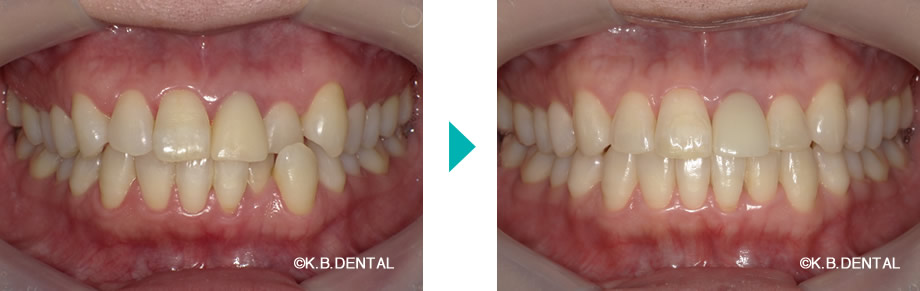

前歯の叢生が目立つ症例

| 主訴 | 上下の歯並びが気になる。左上1番の古いセラミックも歯並び直した後に交換したい |

|---|---|

| 診断名 | 叢生 |

| 初診時年齢/性別 | 43歳女性 |

| 装置 | マウスピース矯正(インビザラインGo)+セラミック治療 |

| 抜歯/非抜歯 | 非抜歯 |

| 治療期間 | 約1年 |

| 費用 | 約80万円(税別) |

| リスク副作用等 | 矯正歯科治療のリスク副作用について |